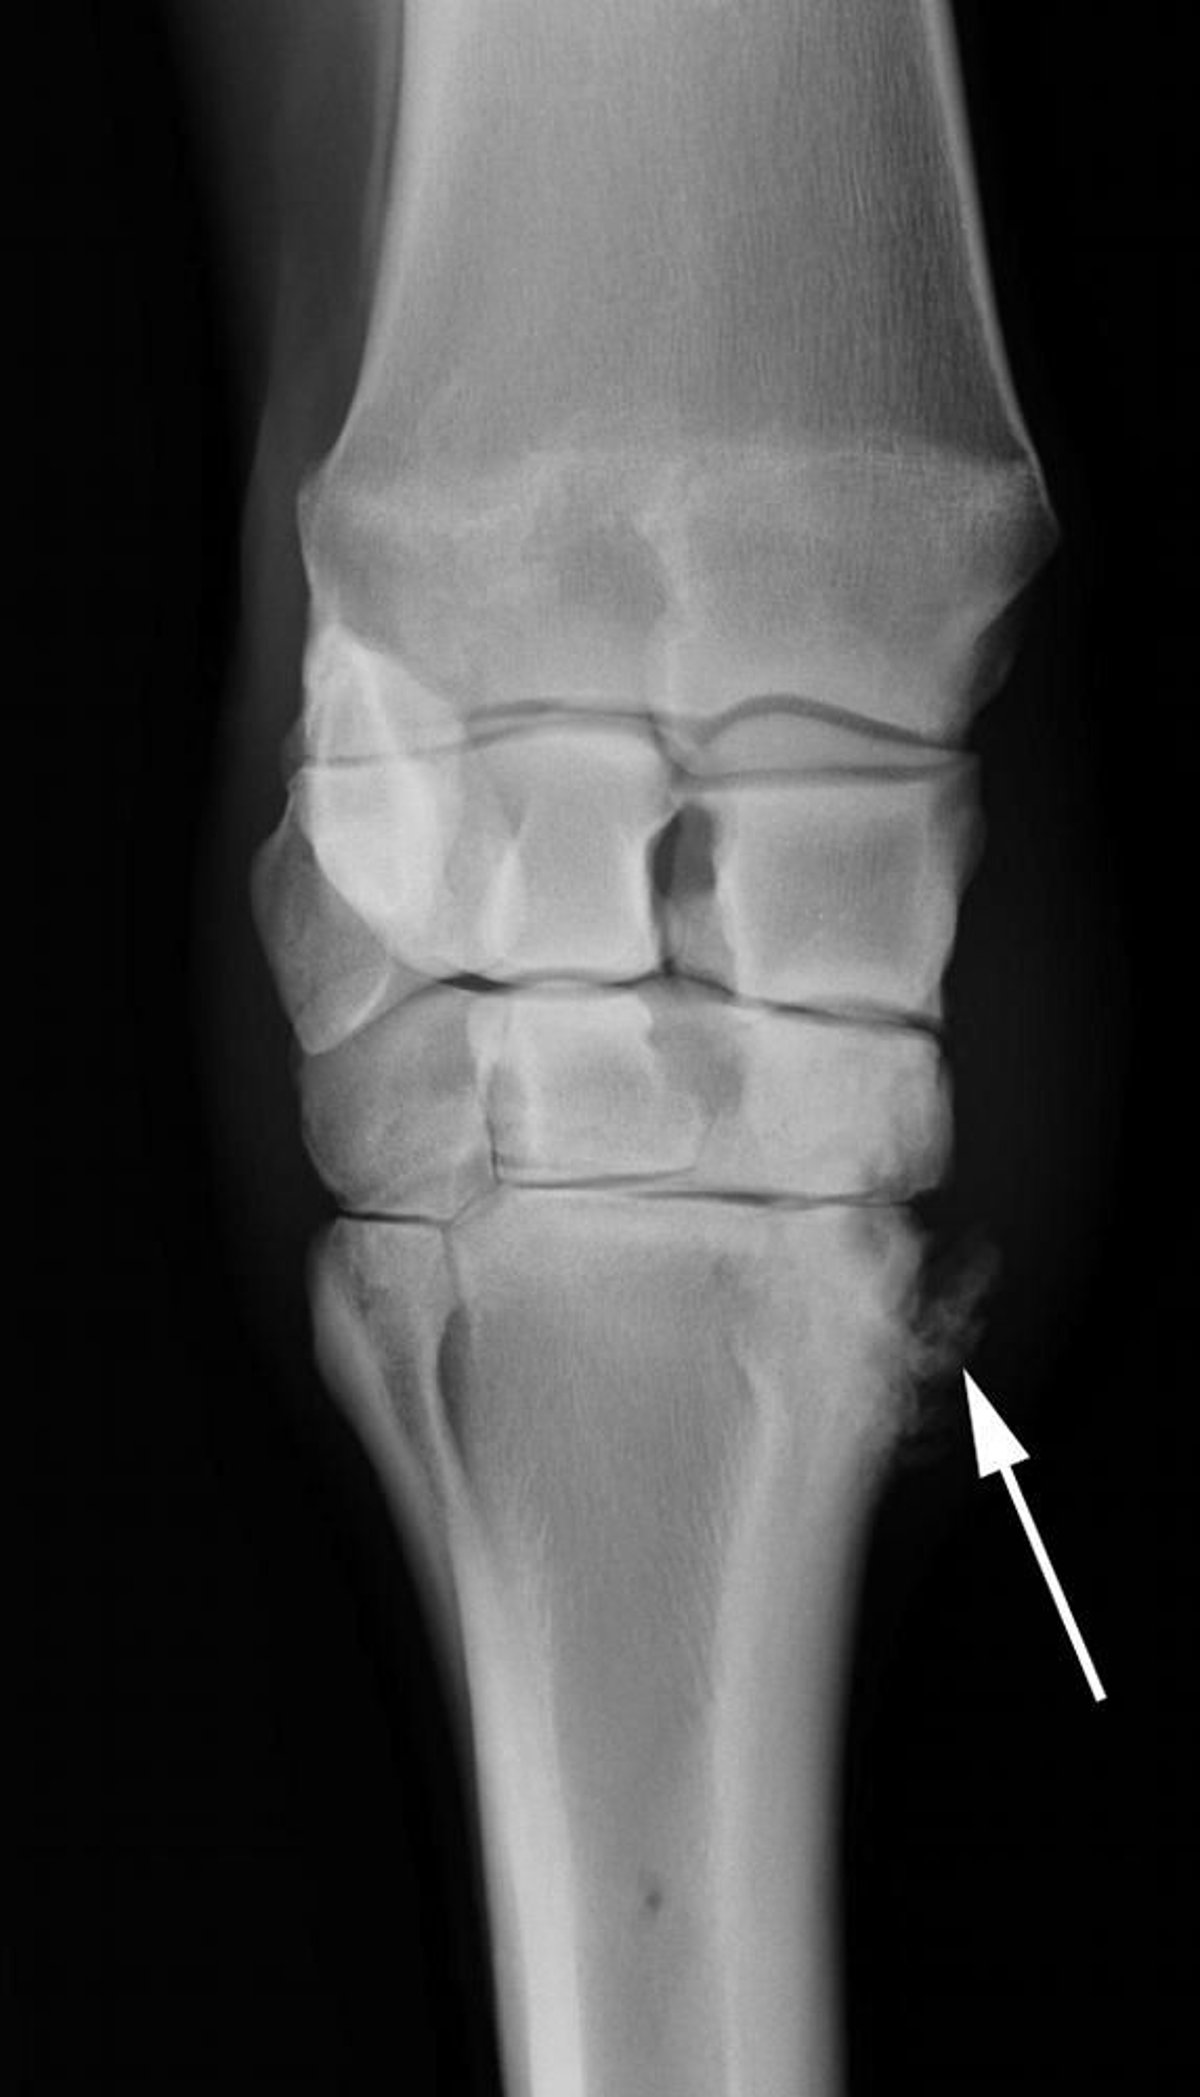

Radiograph showing marked new bone proliferation (arrow) in a horse with osteoarthritis of the carpometacarpal joint.

Courtesy of Dr. Matthew T. Brokken.